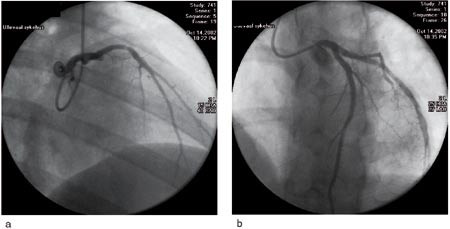

Pasienten. En tidligere stort sett frisk 27 år gammel mann ble innlagt pga. akutte brystsmerter. EKG viste ST-elevasjon i avledning V₁ – V5, forenlig med akutt ST-elevasjonshjerteinfarkt. Han ble straks sendt til koronar angiografi, hvor det ble påvist en stor okkluderende trombe proksimalt i venstre fremre koronararterie (fig 1a). Høyre koronararterie hadde en ikke-signifikant stenose i midtre del. Det ble utført ballongdilatasjon med stentimplantasjon av den okkluderte arterien ca. 90 minutter etter smertedebut (fig 1b). Pga. tegn til perifer embolisering fikk han tilleggsbehandling med platehemmeren abciximab intravenøst.